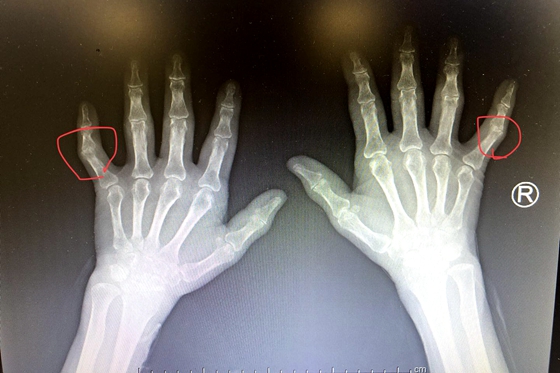

患者关节间隙变窄骨质融合